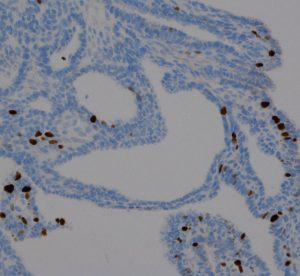

Monomorphous mass of well-differenciated squamous epithelium lacking surface maturation and wet keratin.

摘出した骨化片の病理像です。成熟した骨組織 mature boneです。